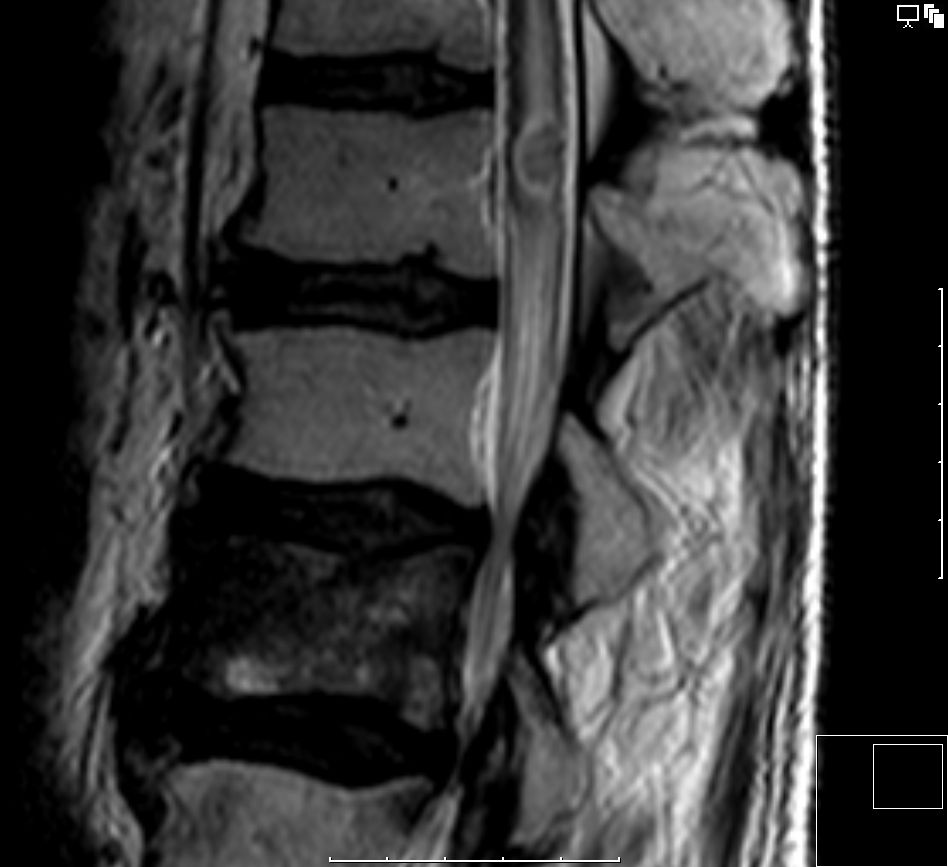

| Rückenmarksmetastasen | 60-jähriger Patient, der nach Prostata- und Nierenkarzinom ein Adenokarzinom des rechten Lungenoberlappens entwickelte. 1 Jahr später eine L3-Metastase, die

bestrahlt wurde. Jetzt eine intramedulläre Herdsetzung bei L1.![]() | |||